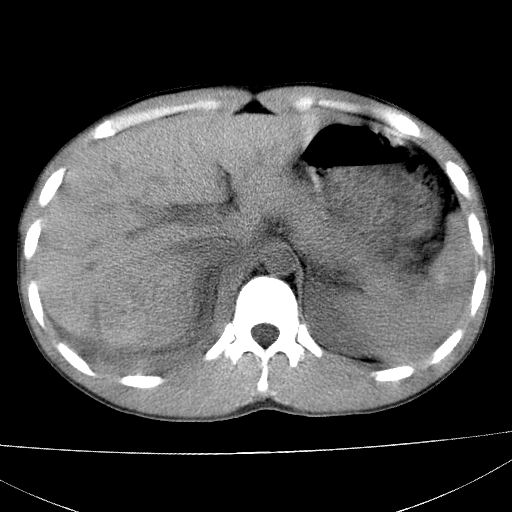

标题: CT15860:男,21岁,腹部外伤2小时伴胸疼。 [打印本页]

标题: CT15860:男,21岁,腹部外伤2小时伴胸疼。

肝脏及肾脏明显有损伤性改变并激发腹腔内积液(血),以肝脏撕裂及肾周积血显著。

1)肝破裂伴腹腔积液(血)。2)右肾破裂伴右肾包膜下及肾周血肿。3)腹部空腔脏器穿孔可能。4)右侧少量胸腔积液(血)。

肝右肾挫裂伤,右肾包膜下及肾周血肿.胸腹腔少量积液.脾脏下部密度稍不均,必要时,增强.